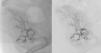

Neste contexto, decidiu-se efetuar angiografia invasiva por acesso arterial femoral direito. Este exame evidenciou fluxo muito escasso na artéria renal do enxerto e imagens hipotransparentes múltiplas e difusas, sugestivas de trombos organizados ao longo de todo o trajeto da artéria renal do rim transplantado (Figura 1). Procedeu-se a canulação seletiva com cateter de mamária interna e introdução na artéria renal de fio guia Balance Middleweight Universal II 0,14” (Abbott vascular®). De seguida, utilizando o sistema de aspiração por cateter Pronto V3 6F (vascular solutions, Inc.®), procedeu-se à aspiração de conteúdo intra-arterial, confirmando-se macroscopicamente a existência de material com aspecto trombótico (Figuras 2–4). Posteriormente, efetuou-se angioplastia com balão em toda a extensão da artéria renal (Figura 5). A melhoria angiográfica foi imediata, com visualização da sombra renal, evidenciando-se, no entanto, discretas irregularidades parietais (Figura 6). A terapêutica farmacológica adjuvante instituída consistiu em ácido acetilsalicílico (100mg/d), heparina não fracionada (5000U/bólus seguida de 100 U/kg/h) durante 72h e, subsequentemente, hipocoagulação oral com varfarina (INR alvo 2,0-3,0).

Aos 30 dias de seguimento, verificou-se novo agravamento da função renal (Cr 4,09mg/dl), repetindo-se a angio-TC e subsequentemente a angiografia renal. Devido à presença de reestenose foi efetuada nova angioplastia da artéria renal do aloenxerto, utilizando a mesma técnica do primeiro procedimento, embora com implantação de um stent farmacológico com everolimus Promus Element 3,0/28mm a 16 atm (Boston Scientific®) (Figuras 7 e 8). Após esta intervenção, o doente evoluiu favoravelmente e os 3 meses de seguimento decorreram sem recidiva do quadro ou outros eventos clínicos relevantes.